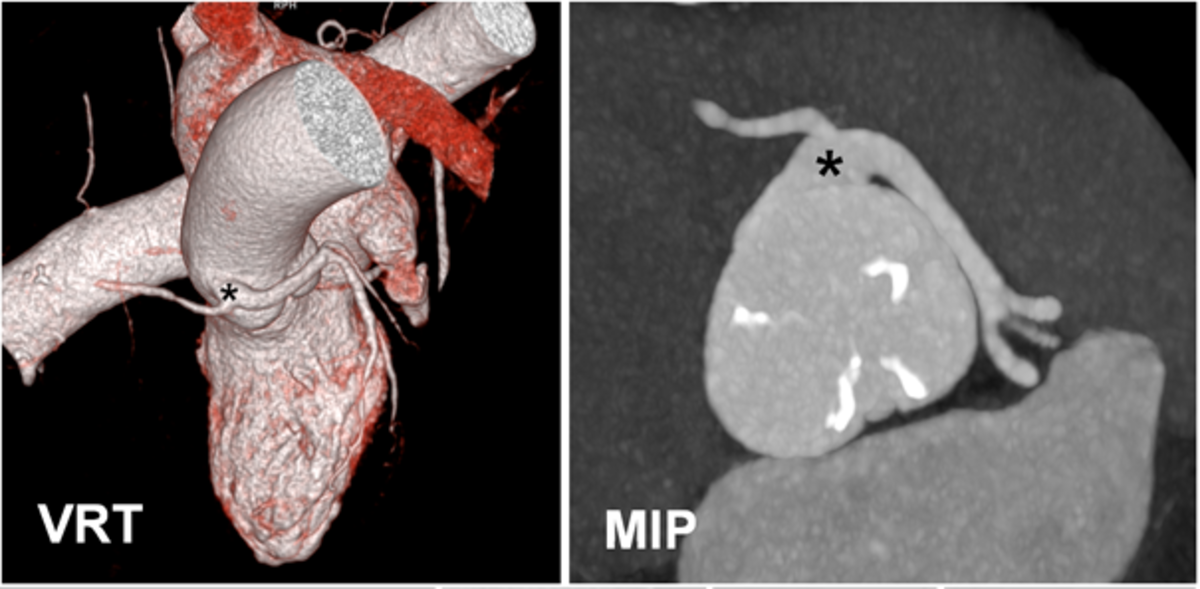

2) Verdacht auf angeborene Anomalien der Koronararterien:

Bei dieser 80-jährigen Patientin fiel bei der Herzkatheteruntersuchung ein ungewöhnlicher Verlauf der Koronararterien auf. Die CT-Koronarangiographie lässt die genauen anatomischen Verhältnisse sehr schön erkennen: Es liegt ein gemeinsamer Ursprung sämtlicher Koronararterien im Bereich des rechten Koronarostiums vor (*) mit Verlauf des linken Hauptstamms zwischen der Lungenarterie und der Aorta auf die eigentlich linke Herzseite. Häufig sind dies auch Zufallsbefunde, die jedoch gerade bei jüngeren Patienten eine therapeutische Konsequenz haben können.